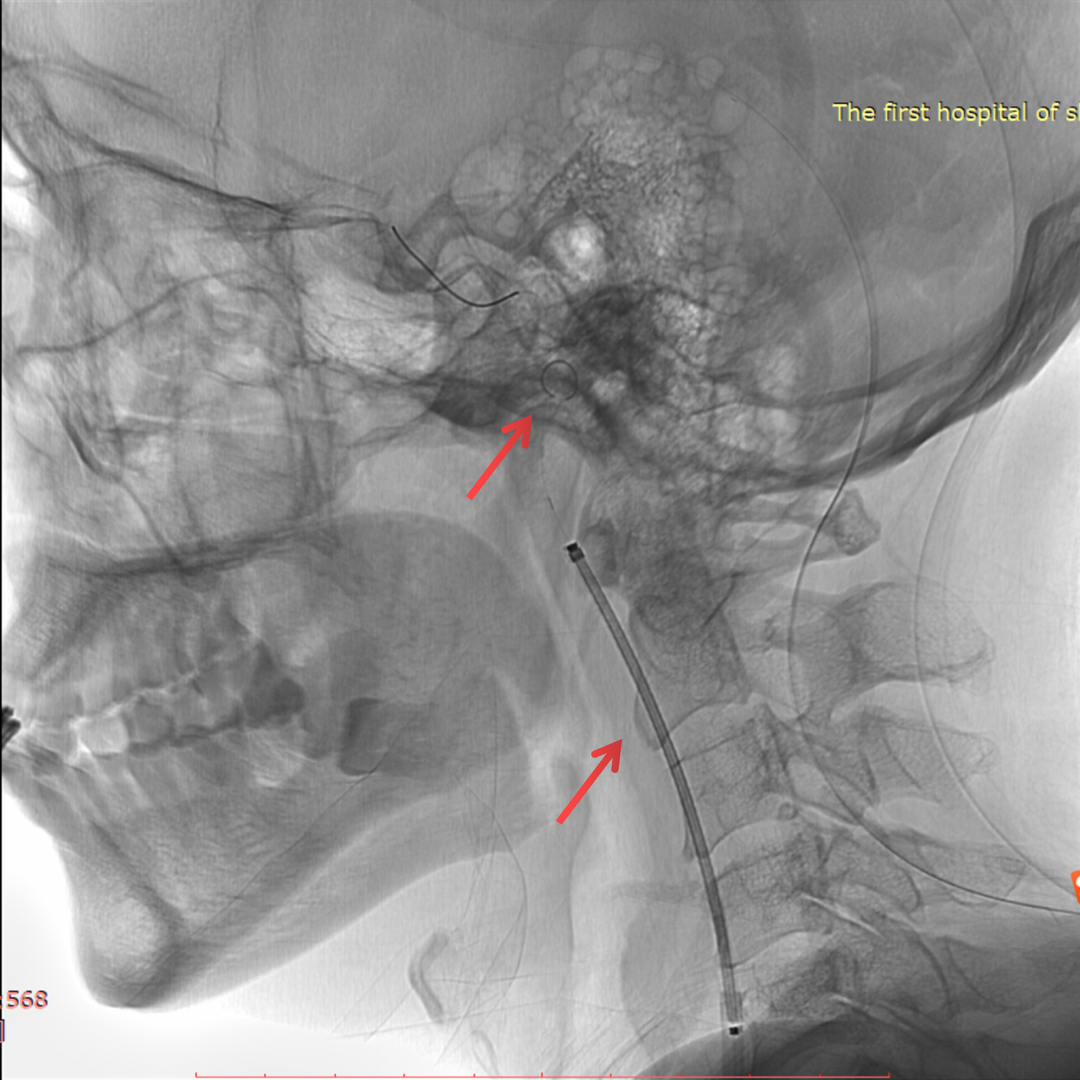

术后情况

术前、术后对比

总结

• 本患者血管相对迂曲,斑块不稳定,选用Filterwire保护伞+Wallstent支架,既保证了通过性,也能减少栓塞事件的发生;

• 选用Wallstent支架,同时可以让系统通过变得容易,便于球囊、长鞘或导引导管的通过,便于后扩张及避免收伞困难;

• 球囊后扩可改善支架贴壁情况,同时可以缩短手术操作时间,但也要注意可能带来的支架短缩的问题。